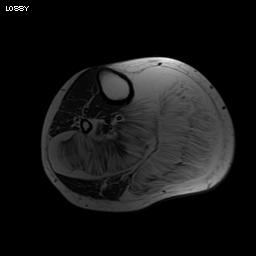

MRI

Same signal intensity as surrounding fat

Intra-muscular lipoma